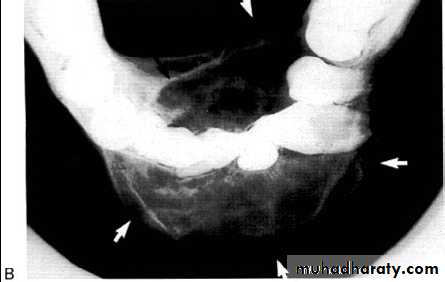

• Aneurysmal Bone Cyst

Large multilocular aneurysmal bone cyst

in the ramus with marked expansion andthe displacement of/8.

It is non-neoplastic ,exaggerated , localized, proliferative lesion of vascular tissue, containing giant cells.

It’s a variation of the central giant cell granuloma , can be diagnosed only by histological examination